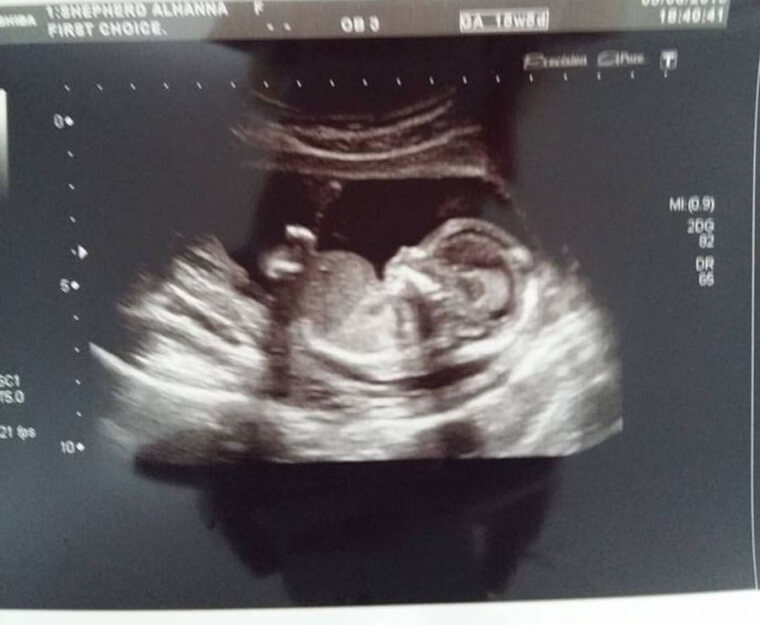

After several failed attempts it all started to feel like a distant dream, but then one day, Alhanna received the most awaited news of her entire life: she was pregnant.

Pregnancy was like a breeze for Alhanna. She had just hit 16 weeks when she suddenly started to experience some really sharp pains in her lower back.

After running a thorough exam and a series of tests, doctors came back with concerning news. Alhanna had a double kidney infection.